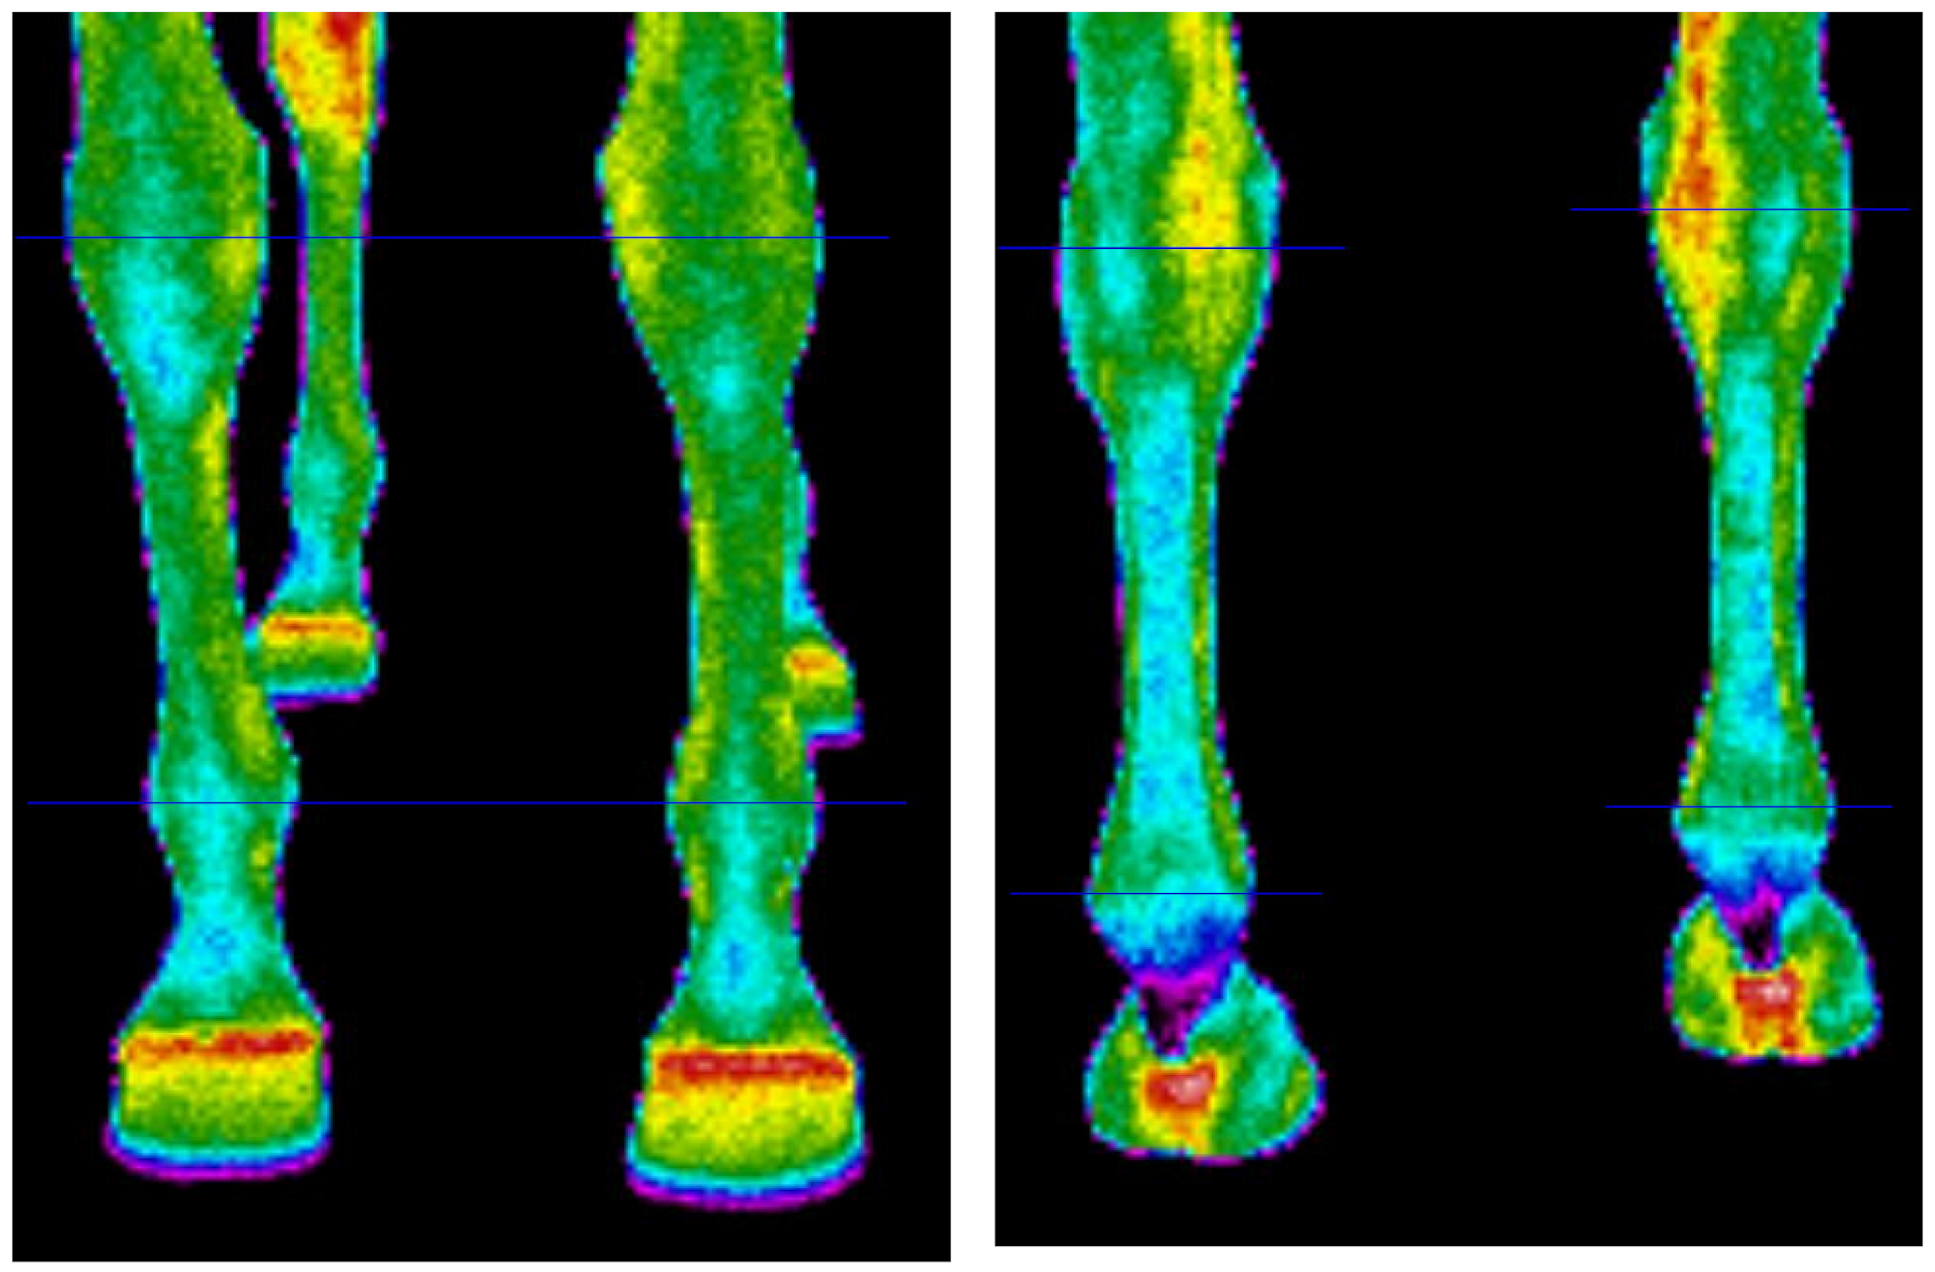

2.5. Thermographic Measurements

| Analysed Surface Area | Leisure Horses (n= 24) | Jumping Sport Horses (n = 24) | ||||

| A | B | C | A | B | C | |

| Metacarpus dorsal | 28.51 ± 0.51 a | 31.72 ± 1.21 a | 31.27 ± 0.97 a | 30.42 ± 0.53 a * | 31.82 ± 1.35 ab | 31.44 ± 1.19 ab |

| Metatarsus dorsal | 27.71 ± 0.46 b | 29.36 ± 0.79 b | 29.02 ± 0.93 b | 30.07 ± 0.51 a * | 31.44 ± 1.01 a * | 30.44 ± 1.26 a * |

| Metacarpus plantar | 28.10 ± 0.49 ab | 33.12 ± 1.42 c | 32.53 ± 1.40 a | 28.72 ± 0.48 b | 33.50 ± 1.33 b | 32.60 ± 1.03 b |

| Metatarsus plantar | 28.49 ± 0.50 a | 30.95 ± 1.48 ab | 30.15 ± 1.57 b | 29.17 ± 0.49 b * | 32.55 ± 1.47 ab * | 31.25 ± 1.64 ab |